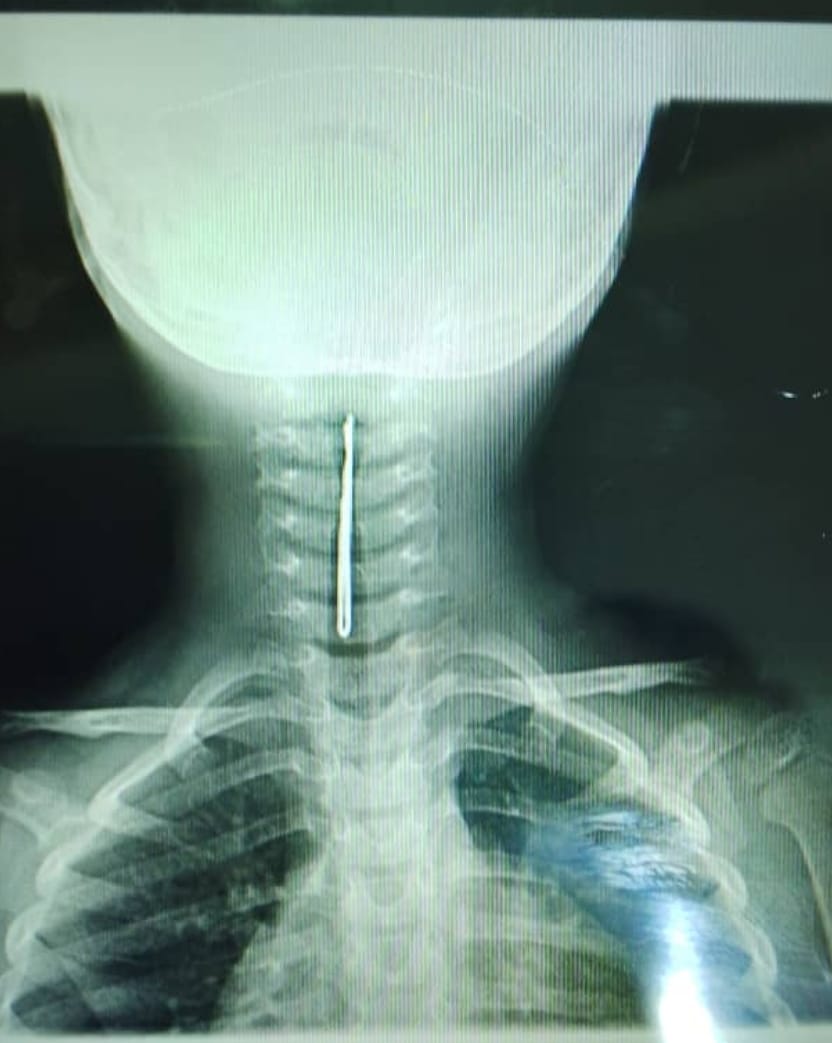

@tanganyika_hosp

TANGANYIKA HOSPITAL

2 months

Image du jour. Merci à notre équipe ORL et d'anesthesie réa d'avoir sauvé cet enfant (ablation d'une pince à cheveux d ses voies respiratoires). Aux parents d faire également très attention à leurs petits bouts. Nous restons à votre entière disposition pr tout problème d santé